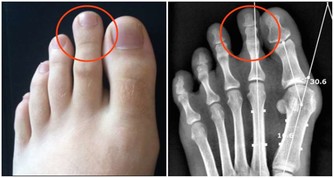

另外,一些慢性腎衰病人還有一些特殊的臨床表現,如口腔內有氨的氣味,也就是你說的尿味,尿毒症病人更為明顯。

主要原因是,隨著腎功能的減退,腎臟的溶質清除率下降和某些肽類激素的滅活減少,造成多種毒素在血液和組織中蓄積,最常見的毒素就是尿素等。

在口腔中,因為唾液中的尿素被分解為氨,故病人呼出的氣體有尿味。

這種氣味的濃淡隨病情的進退而變化,在病情好轉時,口中尿味淡些,病情加重時尿味變濃。